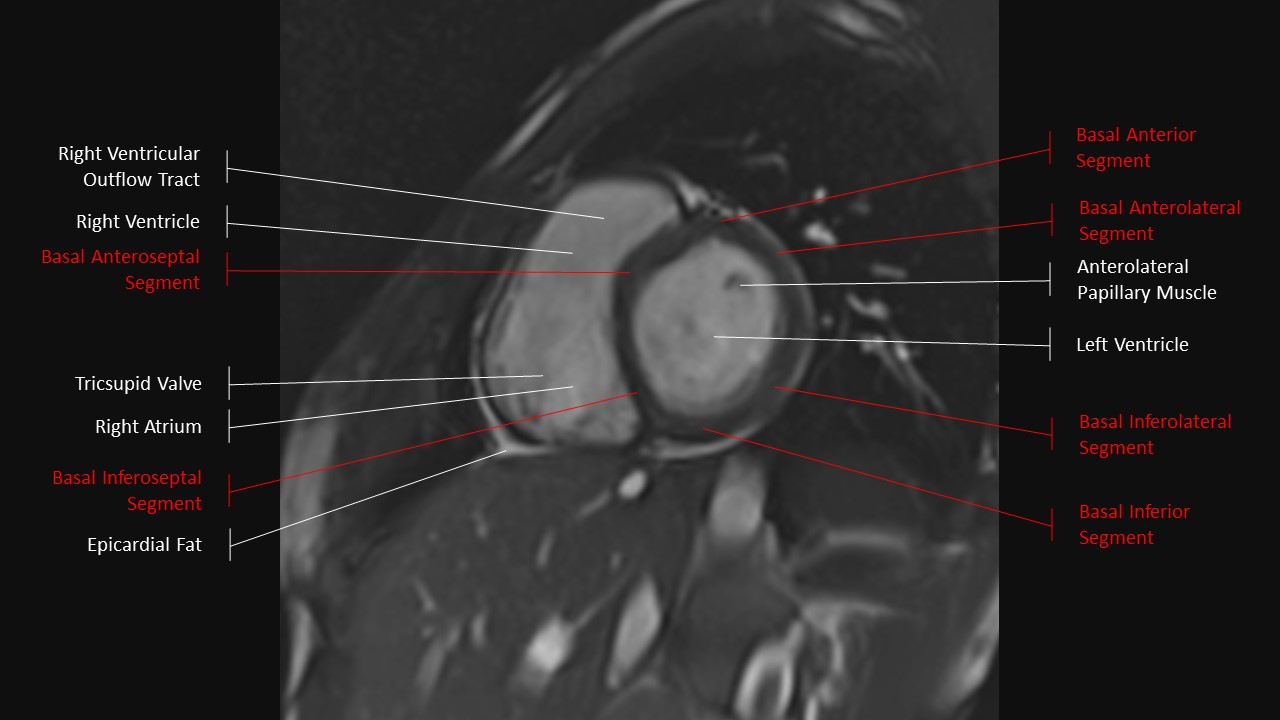

Short Axis Series